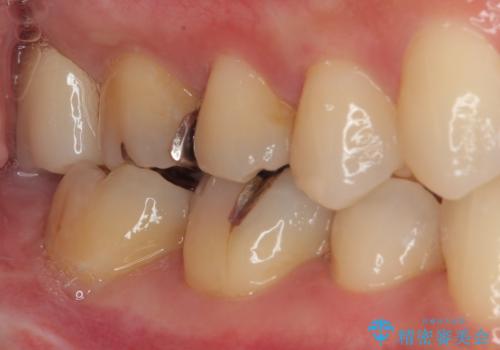

矯正治療により処置が可能な位置に歯が移動したため、オールセラミッククラウンにて補綴治療を行うこととしました。

歯列が移動したとはいえ、左右ともに後方傾斜しており、むし歯の除去、形成(形を整える)、型取りの全てが非常に困難な処置となりました。

セラミッククラウンの適合はレントゲン写真からも分かる通り、境界がぴったりと合った、高適合のものとなりました。